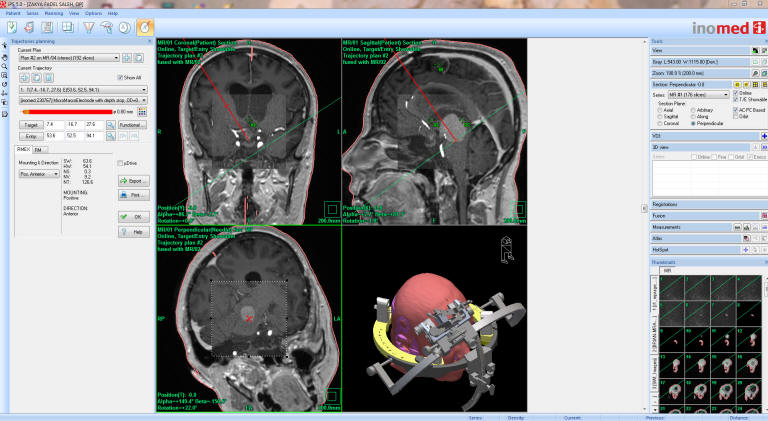

Fig-9: The ceramic ring fixed with localizer and sent to MRI with TxRx head coil to perform coordinated data to the iPs 5 planning software.

Fig-10: The trajectory was exactly planned to have the tube in the most dependant point of the cyst without contaminating the CSF.